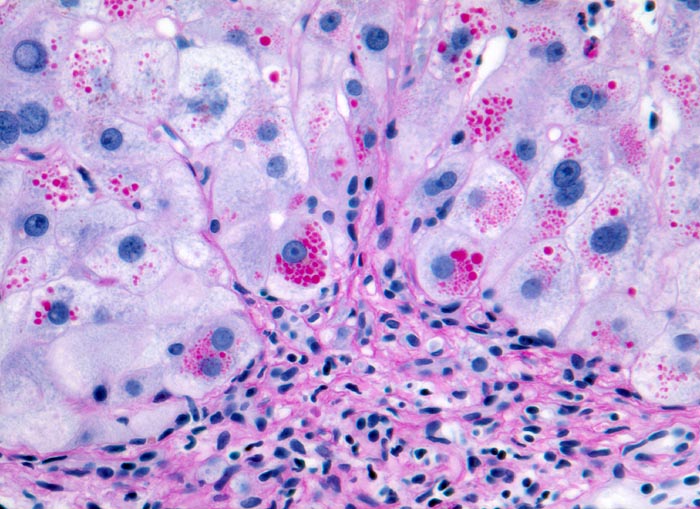

AP/ Leber bei alpha-1-Antitrypsinmangel

Leber bei alpha-1-Antitrypsinmangel